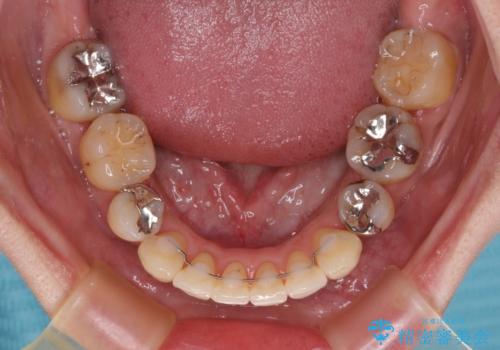

【モニター】上下の八重歯を治したい ワイヤー装置による矯正治療

治療期間全体を通して歯の移動スピードがゆっくりであったので、当初予定よりも1年ほど長い、3年間を要することとなりました。